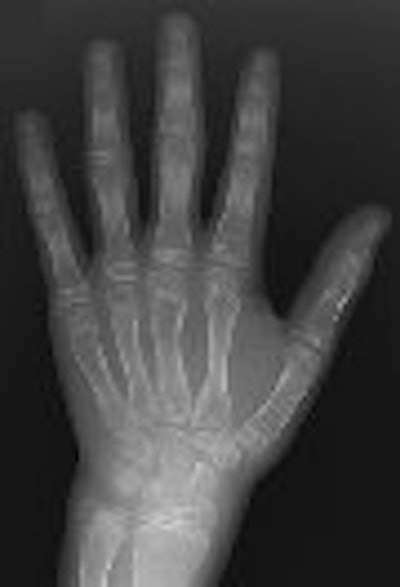

Another characteristic aspect of CACP syndrome is visible in the hands, in the squaring of the metacarpal and phalangeal heads.

![]() |

| Fourteen-year-old boy with camptodactyly-arthropathy-coxa vara-pericarditis (CACP) syndrome. Dorsopalmar radiograph of left hand illustrates that presence of camptodactyly may not always be obvious from radiographs. Arthropathy in CACP syndrome may be associated with periarticular osteopenia. Note absence of erosive change. Although this appearance is consistent with early juvenile idiopathic arthritis, squaring of metacarpals and phalanges (seen in CACP syndrome) helps to differentiate two conditions. Amaka OC, Woo P, Prieur A, Hasson N, Hall CM, "Camptodactyly-Arthropathy-Coxa Vara-Pericarditis Syndrome Versus Juvenile Idiopathic Arthropathy" (AJR 2005; 185:522-529). |